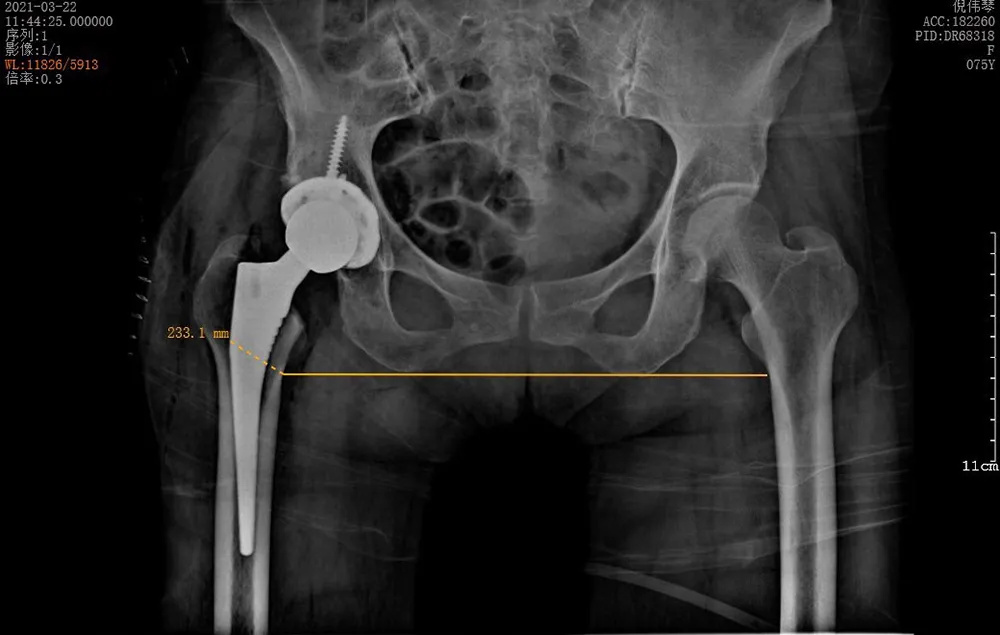

3月22日,在將倪阿姨的身體調(diào)整到最佳狀態(tài)并完善所有術(shù)前準(zhǔn)備之后,羅軍團(tuán)隊(duì)為她進(jìn)行了手術(shù)。術(shù)中發(fā)現(xiàn)其股骨頭完全壞死,而且患者的骨質(zhì)疏松嚴(yán)重,所有操作必須十分小心,幸好有精準(zhǔn)的AI-HIP術(shù)前規(guī)劃,手術(shù)歷時(shí)1個(gè)小時(shí)就成功完成,全程出血不到50ml。

↑術(shù)后雙下肢完全等長(zhǎng)